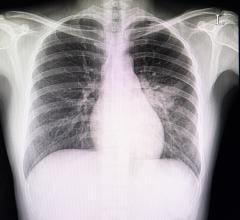

April 17, 2020 — To date, the radiology literature on coronavirus disease (COVID-19) pneumonia has consisted of limited ...

April 14, 2020 — Chest X-rays are often used to detect infections in the lungs, but the world’s largest study of its ...

April 10, 2020 — Radiology departments must prepare for patient surges through streamlined approaches to imaging that ...